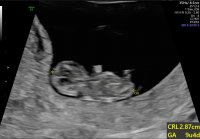

Fikk se en aktiv liten knott i dag 9+2, utrolig kjekt! 2.9 cm, passet bra. Denne gangen til og med med mer menneskeform, utrolig hvor mye som skjer på to uker!

Jordmoren var også veldig grei og betryggende og sa at selv om det ikke finnes noen absolutt garanti mente hun alt så veldig fint ut, godt tegn med bevegelse og dette kom nok til å gå bra. Nå tror jeg at jeg skal klare å senke skuldrene før offentlig TUL i forbindelse med KUB i uke 12 :happy: